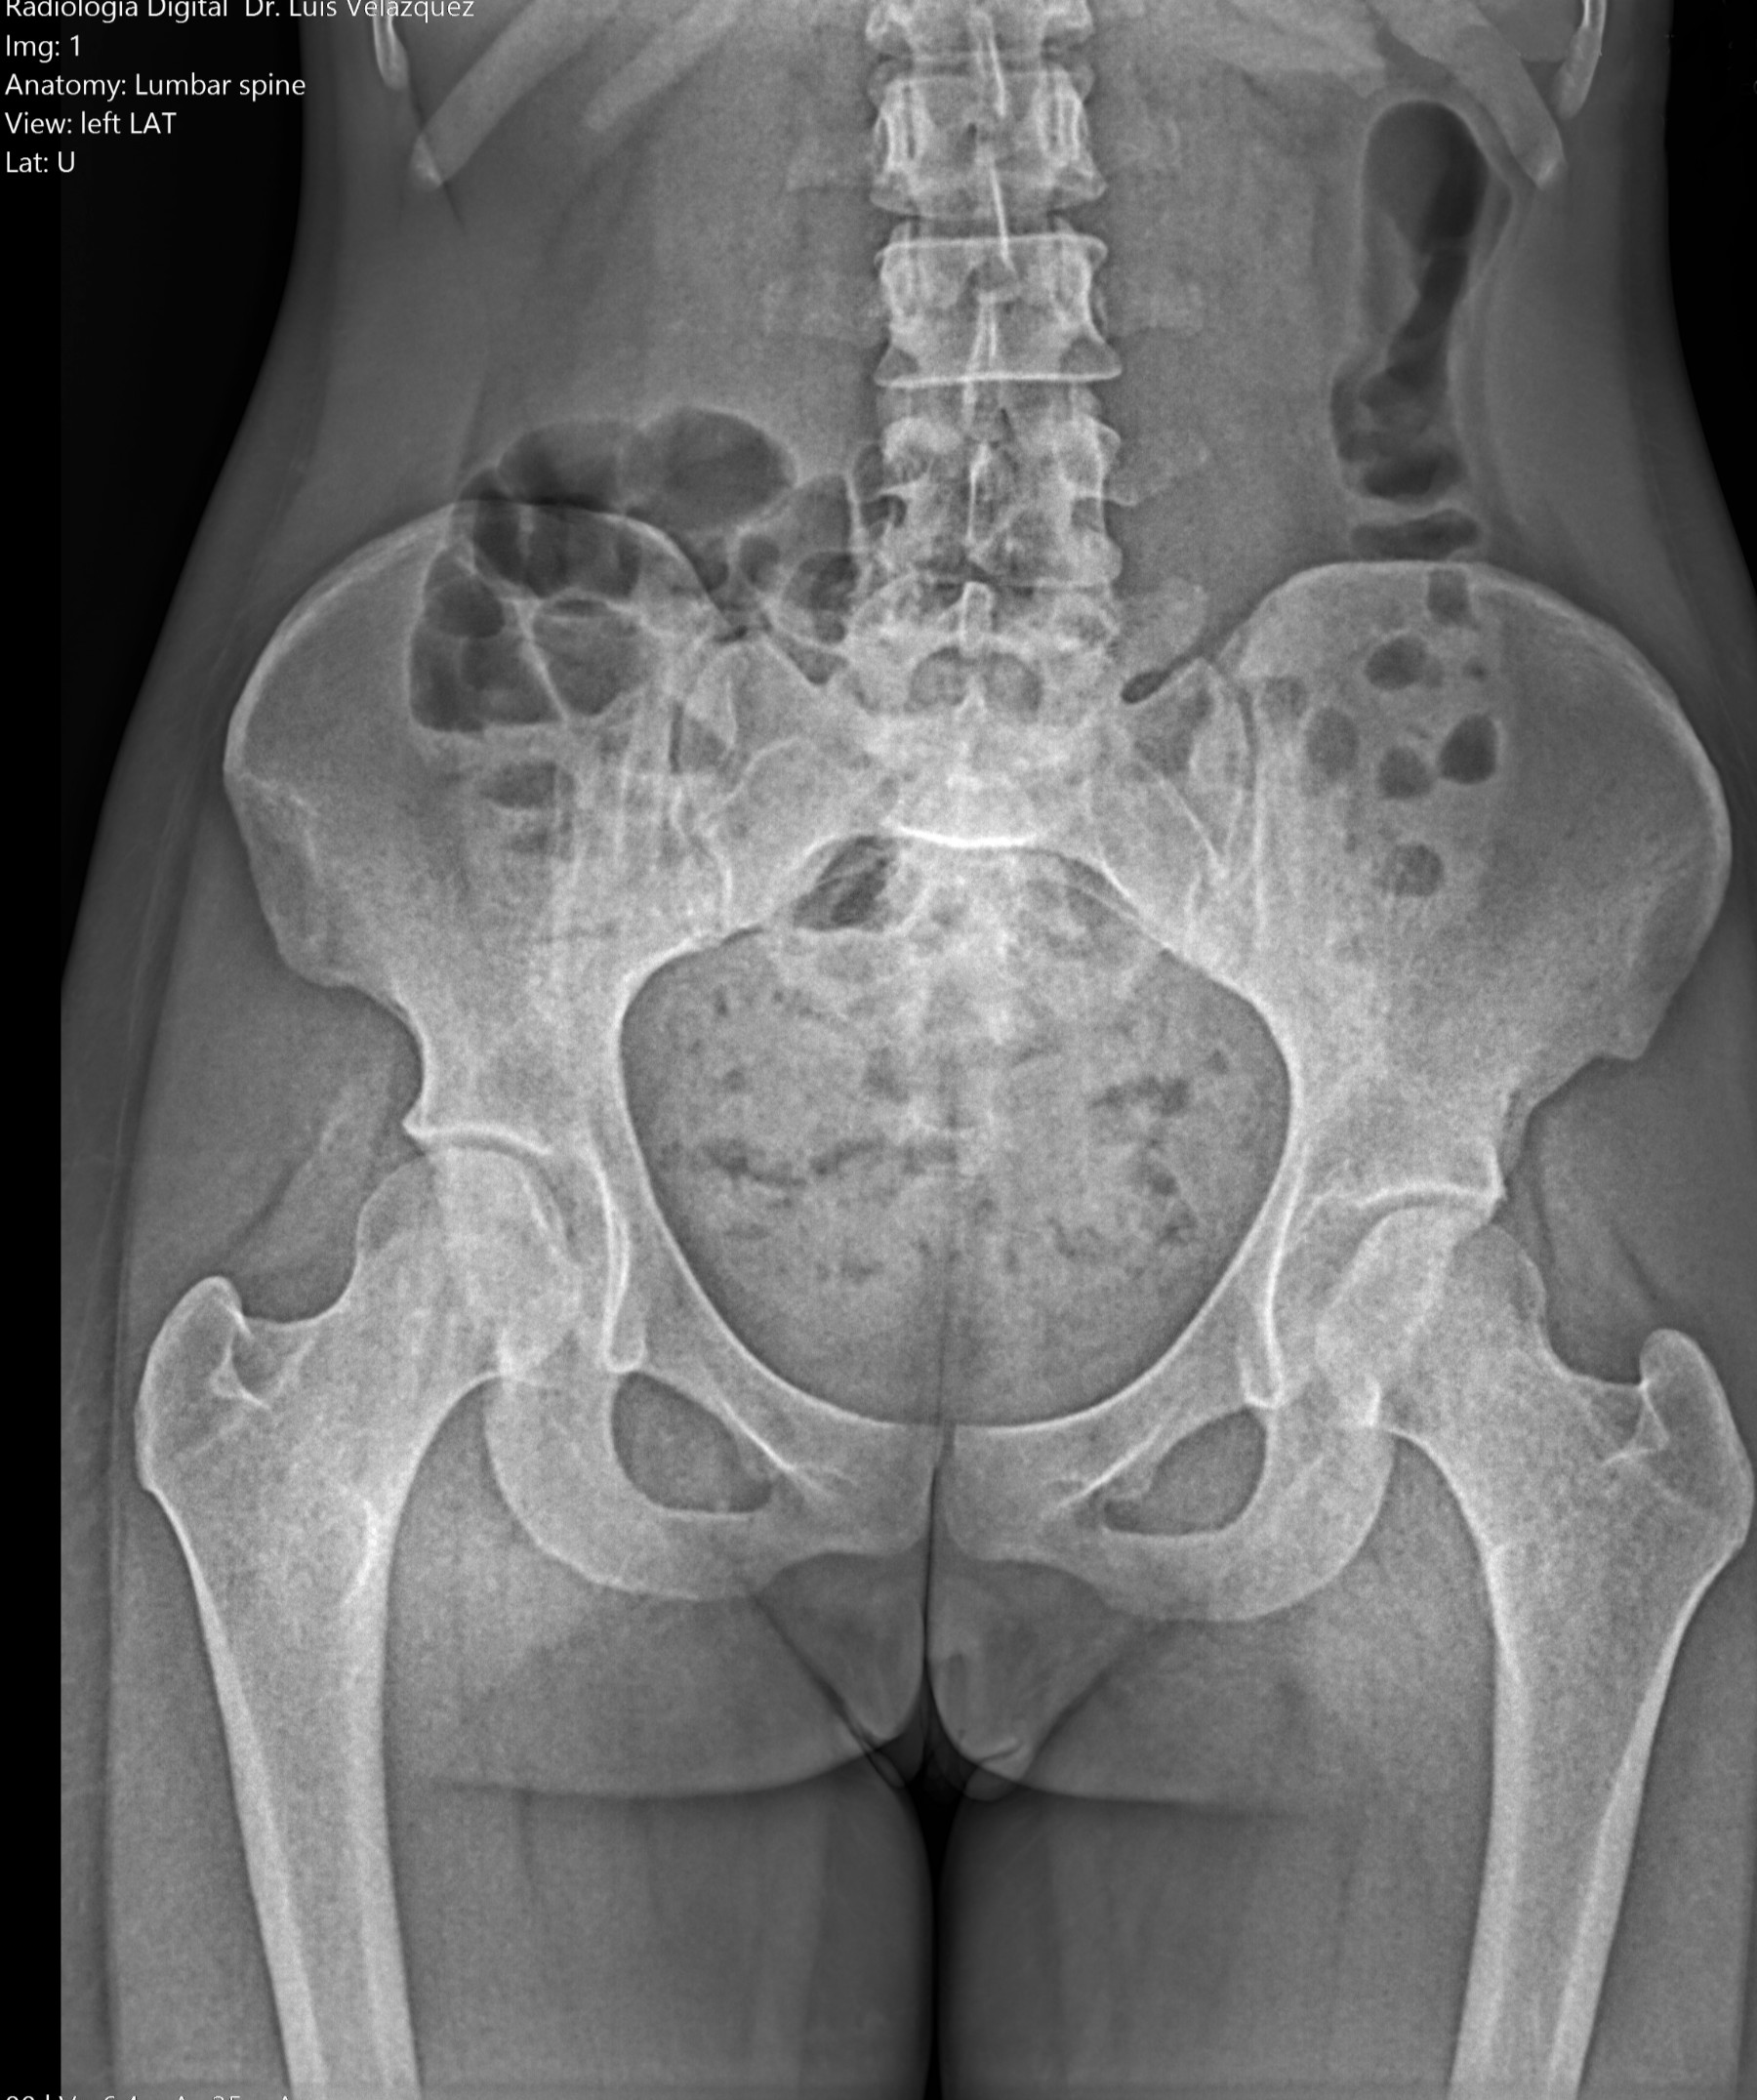

Radiología Digital como Herramienta Complementaria en el Dictamen de Bienes Muebles

Desde el descubrimiento de los rayos “X” y las placas radiográficas por Wilhelm Conrad Roentgen y su posterior difusión a través de la Asociación Físico médica de Wurzburg el 28 de diciembre de 1895, que fue la primera asociación que habló de los nuevos rayos que podían penetrar el cuerpo y fotografiar los huesos, ha habido muchos cambios tanto en la forma de obtener, procesar e incluso en la forma de visualizar, manejar y almacenar las placas radiográficas.